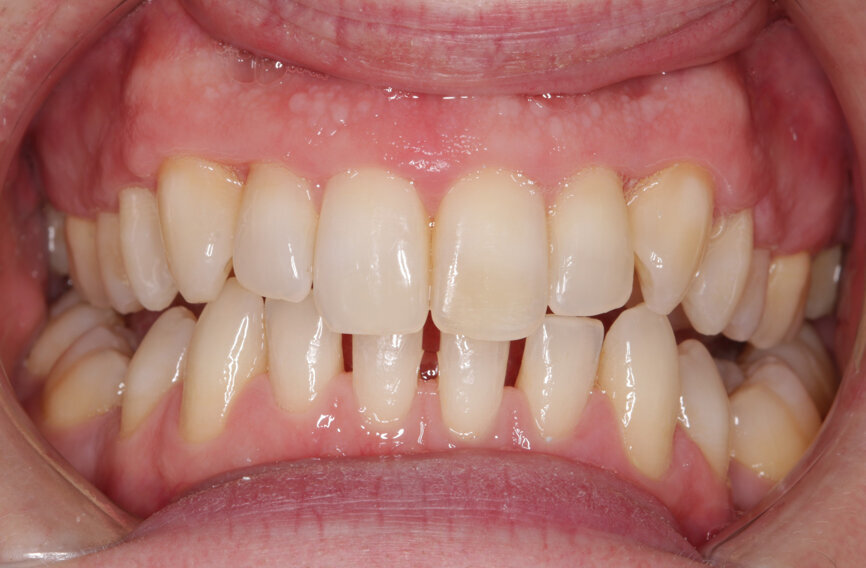

Fig. 2: Pre treatment smile

A 32-year-old male patient presented to our practice after he saw that we provide GDP orthodontics on our website. He came from an NHS practice and it was agreed that he would remain with that practice for his routine care. He was fit and well, took no medication, had no allergies and was a non-smoker. However, he was struggling with his oral hygiene and did not like the appearance of his maxillary teeth, specifically the colour and the alignment. He was not keen on the idea of fixed orthodontic appliances, but had heard about clear aligners.

My examination revealed nothing abnormal with his extra- or intra-oral soft tissue, temporomandibular joint or range of motion. However, his oral hygiene was poor, which was not helped by the crowding of his maxillary anterior segment. In addition, tooth #48 was carious. I carried out a full orthodontic assessment (Table 1) and took photographs.

I explained that the maxillary teeth could and should be aligned, as this would likely result in easier cleaning of the teeth, plus it would improve the appearance. The patient and I agreed that the mandibular teeth could remain untouched, as this would keep the cost down, but mainly because they did not bother him. The priority was to stabilise his periodontal condition. A basic periodontal examination Code 3 and heavy bleeding were recorded in each sextant. At that visit, I performed a gross scaling using the ultrasonic scaler and used a model to demonstrate both the use of flossettes and an oscillating toothbrush.